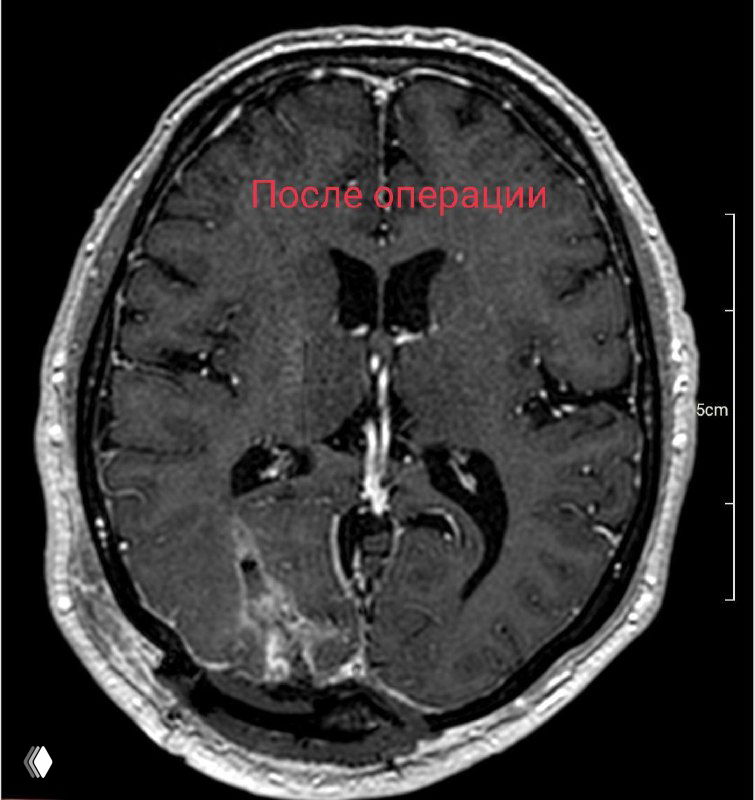

Удаление субкортикальных симптомных каверном в настоящее время безопасный и радикальный метод лечения.